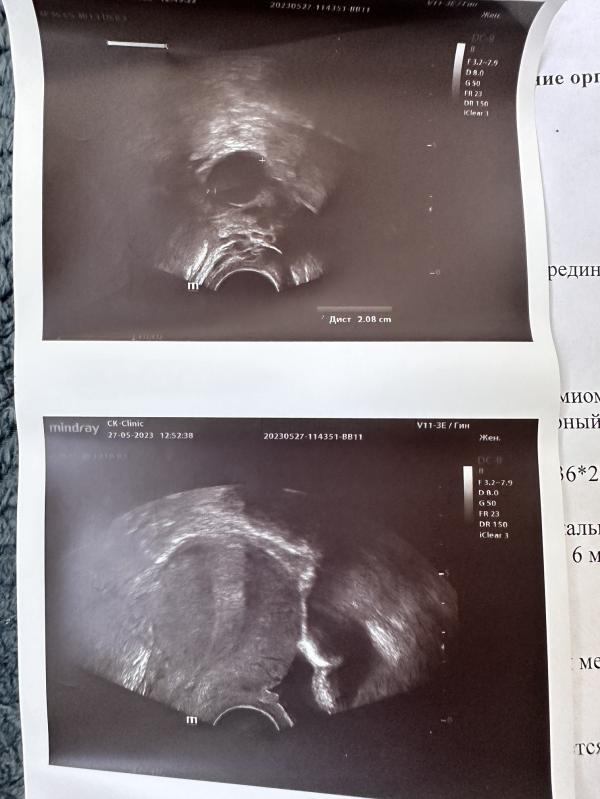

Очередное узи и новый узист в другой клинике. Впервые за 2 года объяснили что за черные кружки онитзамеряют) это большая круглая штука -это доминантный фолликул) который готовится к овуляции. Которая совсем на днях настанет (на фото) 🥲🫶🏻

1. Все идеально на узи. Наконец-то.